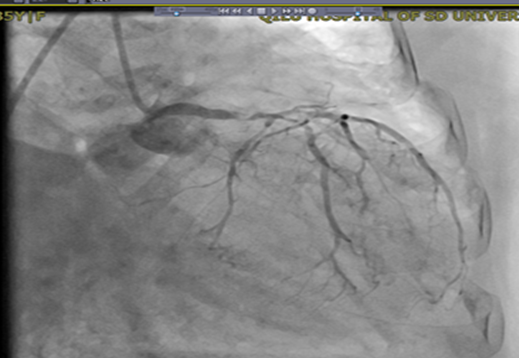

【冠脉造影】

RCA可见钙化影,弥漫性病变,近段狭窄70%,中段狭窄50%,远段狭窄60%,后降支开口95%狭窄。

image012.jpg

LM末端狭窄95%,前降支近段狭窄90%,远段狭窄85%。

LCX弥漫性病变,开口狭窄90%,近段狭窄80%。

造影显示:LM末端狭窄95%,前降支近段狭窄90%,远段狭窄85%,LCX弥漫性病变,开口狭窄90%,近段狭窄80%,RCA可见钙化影,弥漫性病变,近段狭窄70%,中段狭窄50%,远段狭窄60%,建议外科搭桥。